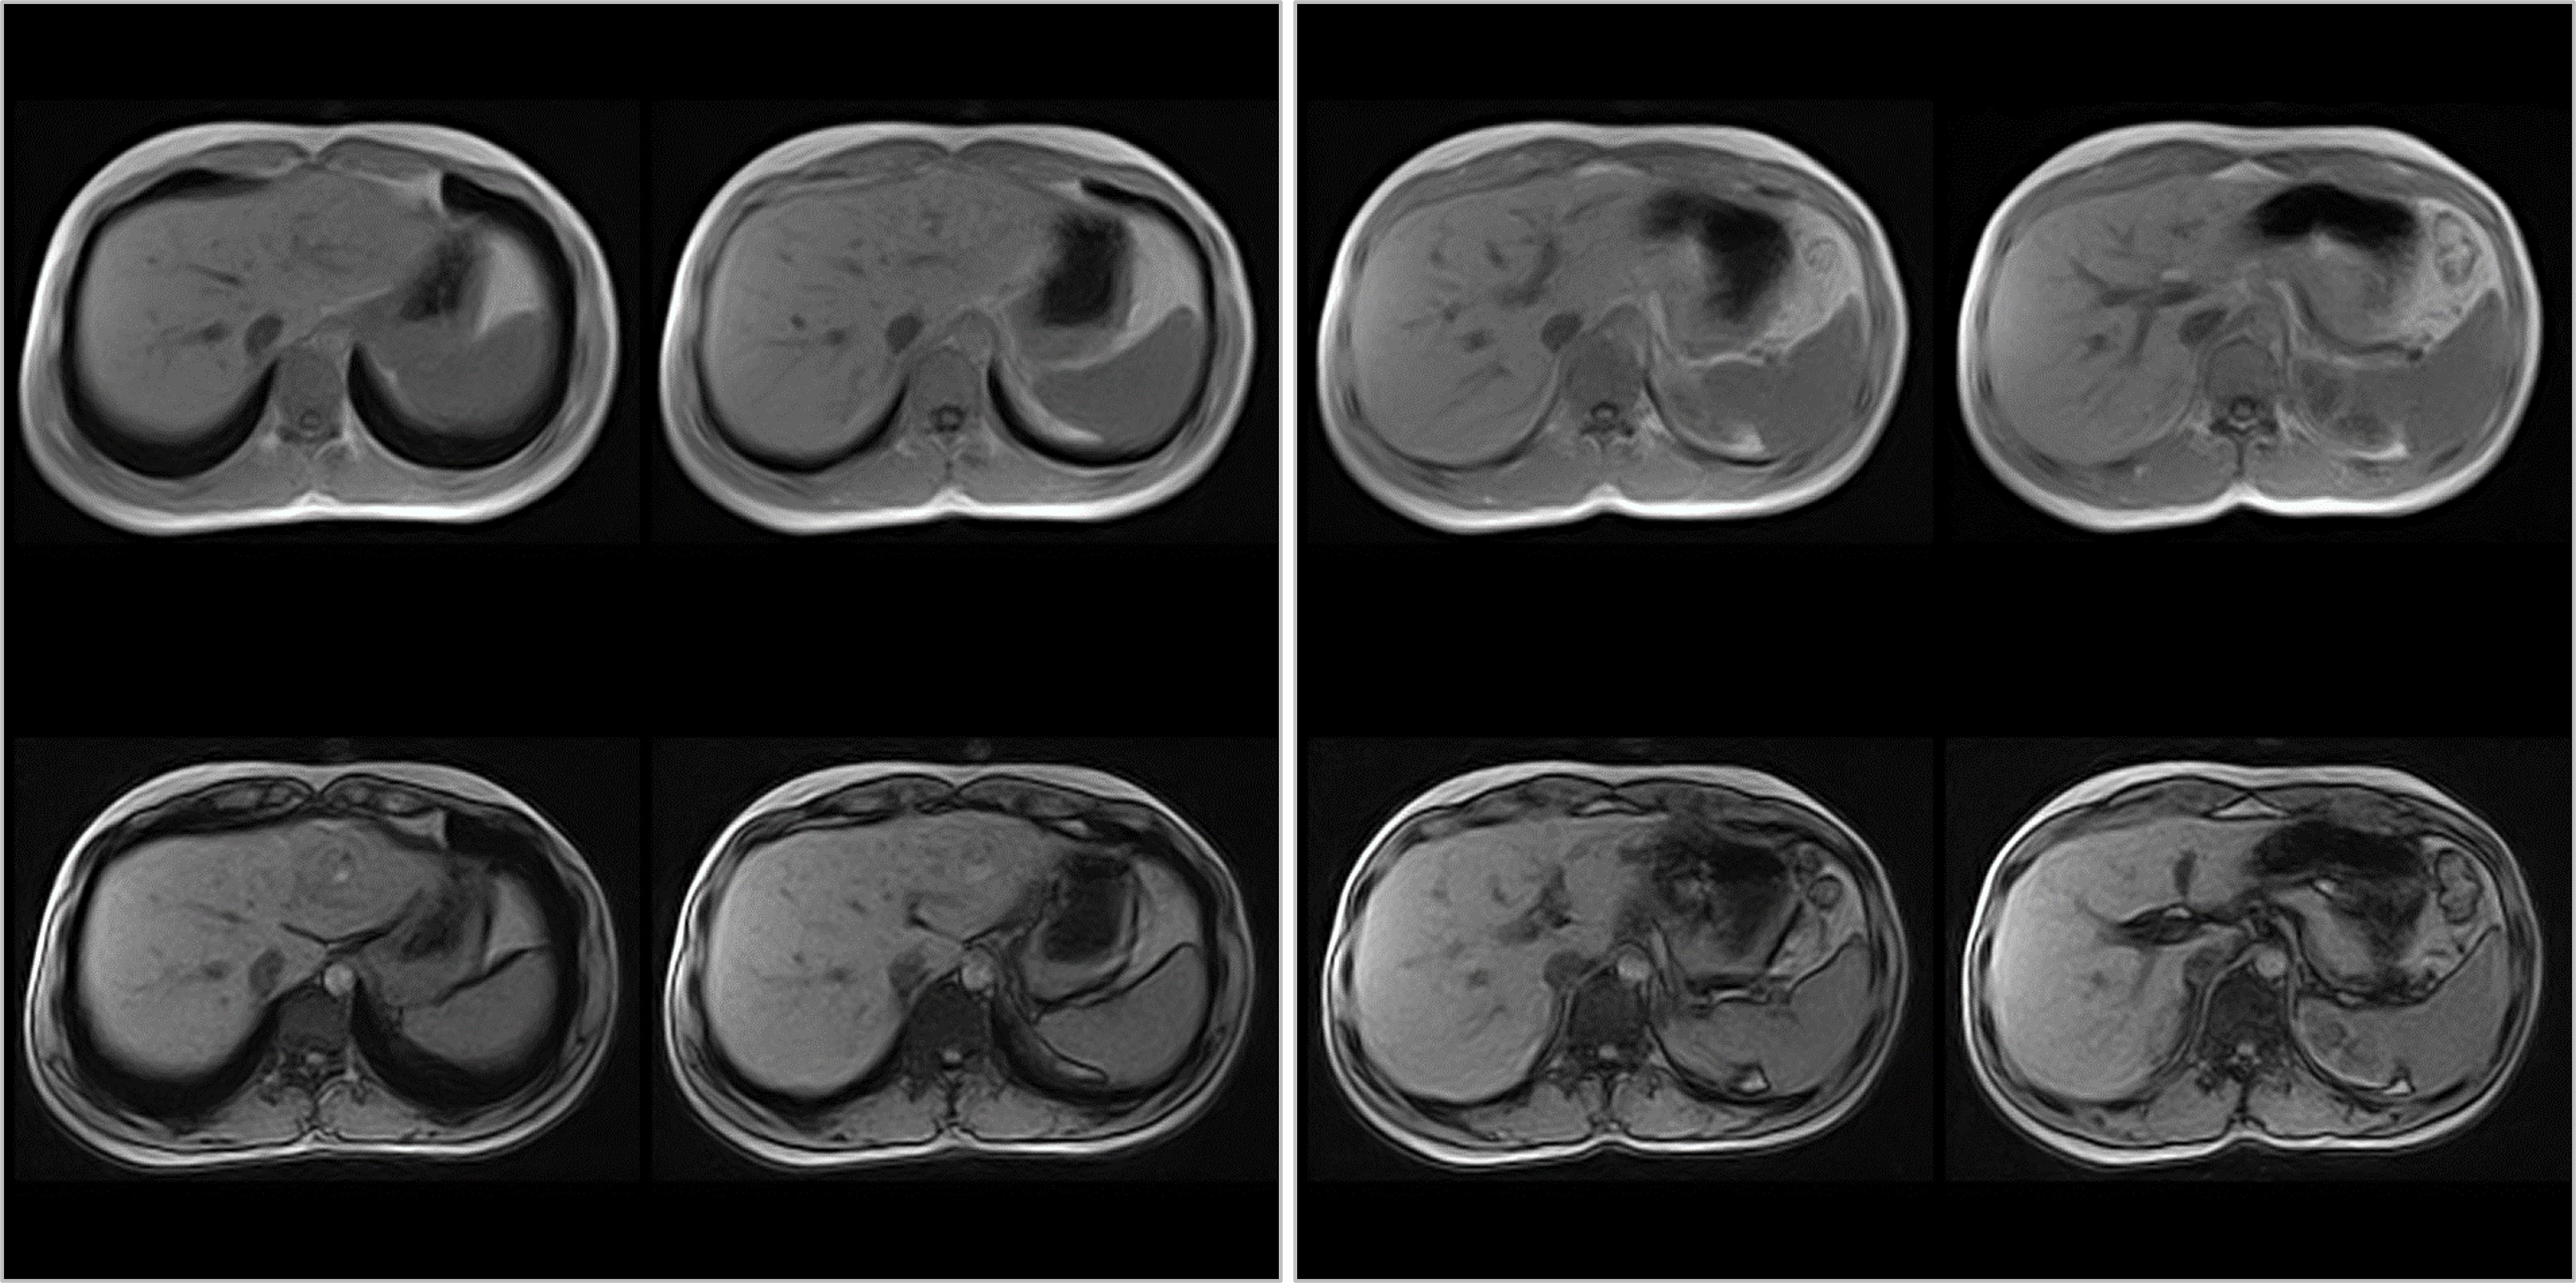

Hình ảnh lâm sàng

Giải pháp lâm sàng ấn tượng